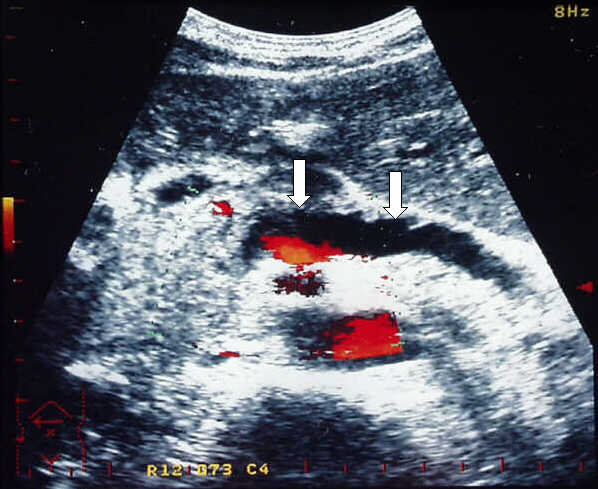

Transverse

Power Doppler scan in a patient with cystic dystrophy of the duodenal wall.

Normal blood flow in the enlarged pancreatic head and severe dilatation (9 mm)

of the main pancreatic duct (arrows).